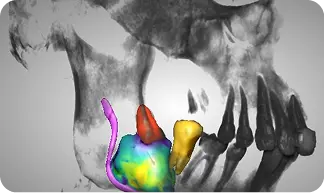

High-precision DICOM conversion into 3D anatomical models and STL files ready for surgical guides.

Accurate, rapid diagnostic analysis for panoramic, cephalometric, and periapical radiographs to support treatment planning.